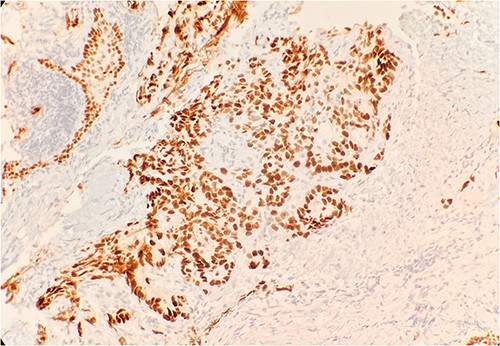

Pathology evaluation from the right middle lobe biopsy showed few clusters of malignant cells, consistent with ADC (Fig. 1). Immunohistochemical staining showed tumor cells were positive for AE1/3, Napsin A and TTF1 (Fig. 2), with ⁓60% Ki-67 positivity. Tumor cells were also negative for CK7 (Fig. 3), p40, p63, CK20 and CK5/6. The overall tumor morphology features and immunoprofile favored moderately differentiated ADC of the lung. However, other primary sites could not be ruled out.

Tumor cells are negative for CK7 by immunohistochemical stain IHC 20×.